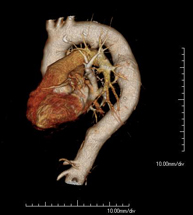

Prueba diagnóstica que consiste en el estudio de la aorta torácica (principal arteria del tórax) mediante el empleo de un equipo de TC (Tomografía Computarizada). Esta técnica requiere el empleo de contraste yodado, y proporciona imágenes de alta definición anatómica. El uso del TCMD (TC Multidetector) acorta el tiempo de exploración, disminuye la dosis de radiación y mejora la calidad de la imagen. Gracias a los múltiples detectores, en determinados estudios se puede acoplar la obtención de la imagen con el latido cardíaco, técnica que permite el estudio de la válvula aórtica y de la raíz de la arteria aorta (primeros centímetros), donde el latido del corazón suele provocar múltiples artefactos de movimiento. - Angio –TC Artèries pulmonars (estudi TEP, Tromboembòlia pulmonar)

Prova diagnòstica que consisteix en l'estudi de l'aorta toràcica (principal artèria del tòrax) mitjançant l'ús d'un equip de TC (Tomografia Computeritzada). Aquesta tècnica proporciona imatges d'alta definició anatòmica. En la majoria de casos és necessari l'ús de contrast iodat. L'ús del TCMD (TC Multidetector) escurça el temps d'exploració, disminueix la dosi de radiació i millora la qualitat d'imatge. Gràcies als múltiples detectors en determinats estudis es pot afegir l'obtenció de la imatge amb el batec cardíac, tècnica que permet l'estudi de la vàlvula aòrtica i de l'arrel de l'artèria aorta (primers centímetres), on el batec del cor acostuma a provocar falses imatges a causa del moviment. - Angio TC d'artèries pulmonars (estudi Tep, tromboembolisme)